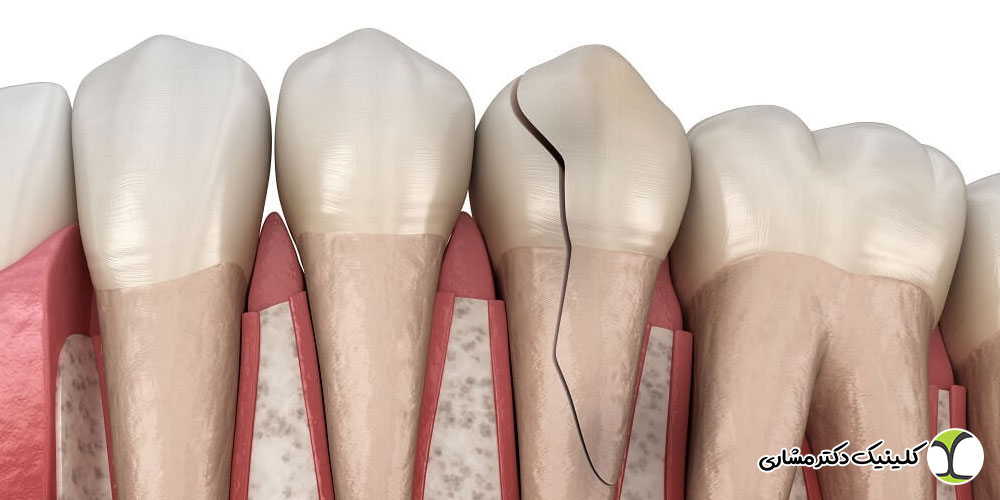

- ترکخوردگی یا شکستگی دندان پس از درمان

ضعیف شدن ساختار دندان

دندانی که درمان ریشه آن کامل نشده، از نظر ساختاری ضعیفتر میشود و در برابر فشارهای جویدن یا ضربه، مستعد شکستگی خواهد بود. در صورت شکستگی شدید، ممکن است دیگر امکان حفظ دندان وجود نداشته باشد.